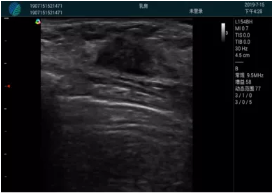

可視化穿刺引導(dǎo)

M20實時引導(dǎo):向包塊后方間隙注射利多卡因

清晰顯示腺體內(nèi)低回聲快影,邊界清晰,包膜較光滑

確定進針路徑并實時監(jiān)測抽吸針與腫塊位置關(guān)系

抽吸針進入腫塊內(nèi)部進行旋切

抽吸過程中可見腫塊明顯縮小,并根據(jù)腫塊位置改變針道位置

抽吸旋切后再進行超聲復(fù)查,原腫塊區(qū)域未見殘留組織及出血

超聲引導(dǎo)下抽吸旋切取出的腫塊組織